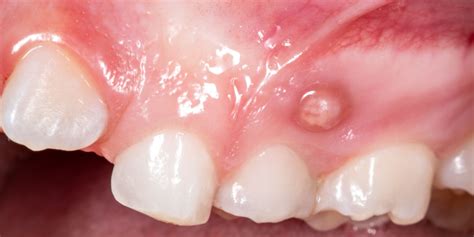

Cuando se forma la fístula dental, aún no causa dolor. Al principio, la zona afectada se hincha. Las encías se enrojecen y hay una sensación de tensión en el diente. A continuación, se forma una ampolla en la encía, encima o debajo del diente afectado, que se llena de pus a medida que avanza. La fístula dental empieza a palpitar y doler. Puede que incluso se te hinche la cara del lado afectado y te duela la cabeza. Esto puede tardar varias semanas en desarrollarse.

Si se ha acumulado mucho pus y la presión es excesiva, la fístula dental se rompe y el pus se drena a la cavidad oral. Pero ¡cuidado! Esto no significa que la fístula dental se haya curado y haya desaparecido. Como la inflamación persiste, todo vuelve a empezar: la fístula dental vuelve a llenarse de pus hasta que estalla de nuevo.

- Absceso dental: Un absceso dental es una acumulación de pus causada por una infección bacteriana en el tejido dental. En el caso de una fístula dental, el absceso puede manifestarse como una protuberancia roja y dolorosa en las encías cerca del diente afectado. Esta protuberancia puede estar acompañada de sensibilidad al tacto y al calor, así como de hinchazón en el área circundante. Con el tiempo, la fístula dental se llena de pus y aparece un dolor punzante.

- Drenaje de pus: A medida que se llena, se forma una pequeña protuberancia en forma de grano cerca de las encías. Si se aplica mucha presión, el pus drena hacia la cavidad oral.